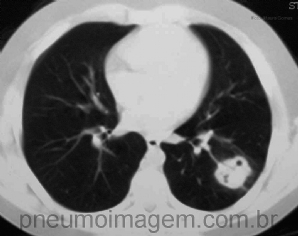

CASO CLÍNICO #38

Menino adolescente de 12 anos de idade com opacidade nodular em lobo inferior esquerdo. Apresentava exposição a pombos no pátio do colégio em que estudava. Qual o diagnóstico mais provável? Deixe os seus comentários abaixo. ***** Teen boy of 12 years old...